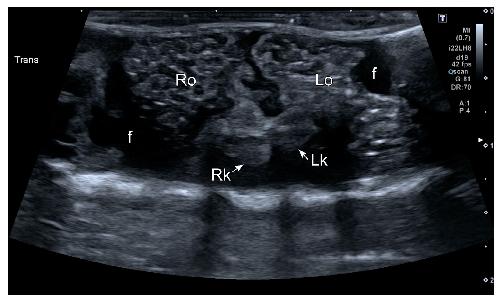

Sex Determination in Two Species of Anuran Amphibians by Magnetic Resonance Imaging and Ultrasound Techniques. , Ruiz-Fernández MJ, Jiménez S, Fernández-Valle E, García-Real MI, Castejón D, Moreno N , Ardiaca M, Montesinos A, Ariza S, González-Soriano J., Animals (Basel). November 18, 2020; 10 (11):